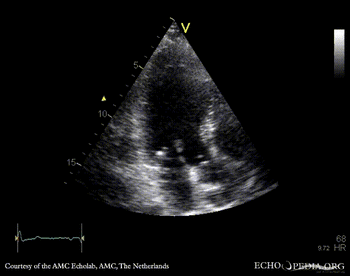

Endocarditis of aortic valve

PLAX: vegetation on aortic valve PSAX: vegetation on aortic valve